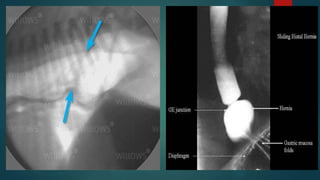

• Hiatal hernias usually appear as a soft tissue or soft tissue/ gas–filled mass

near the esophageal hiatus in the caudodorsal thoracic region on survey

radiographs

• However, with sliding hernias, several radiographs may be necessary to

identify the herniation, which may be intermittent

• The presence of gas in the herniated portion aids in identification of the mass

as herniated stomach

• A positive contrast esophagram should show the gastroesophageal junction,

rugal folds, or both cranial to the hiatus

• Compressing the abdomen during fluoroscopy may help identify hernia

• Some hiatal hernias are intermittent (sliding) and require multiple radiographs

or fluoroscopy (or both) to diagnose